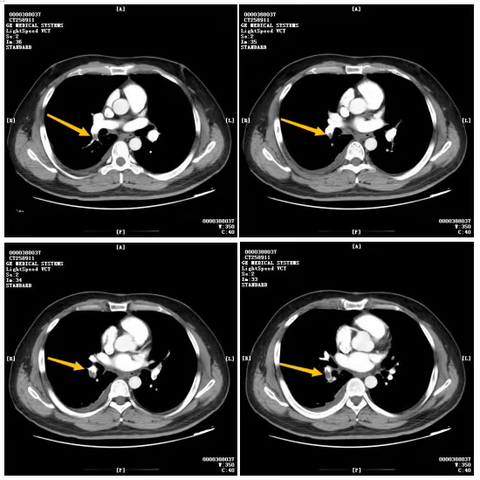

主动脉弓旁小细胞肺癌粒子植入术后纵隔血肿